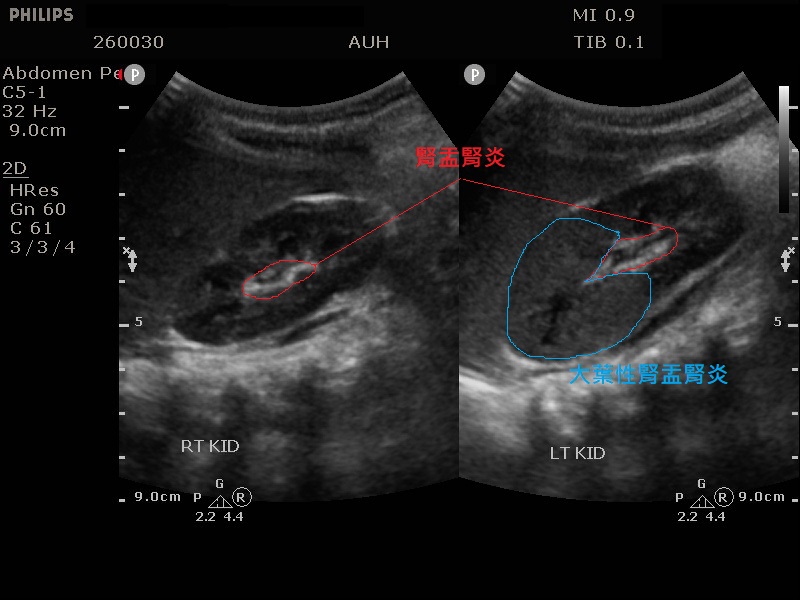

嬰兒高燒不停要注意 大葉性腎盂腎炎 恐害慢性腎衰竭 匯流新聞網